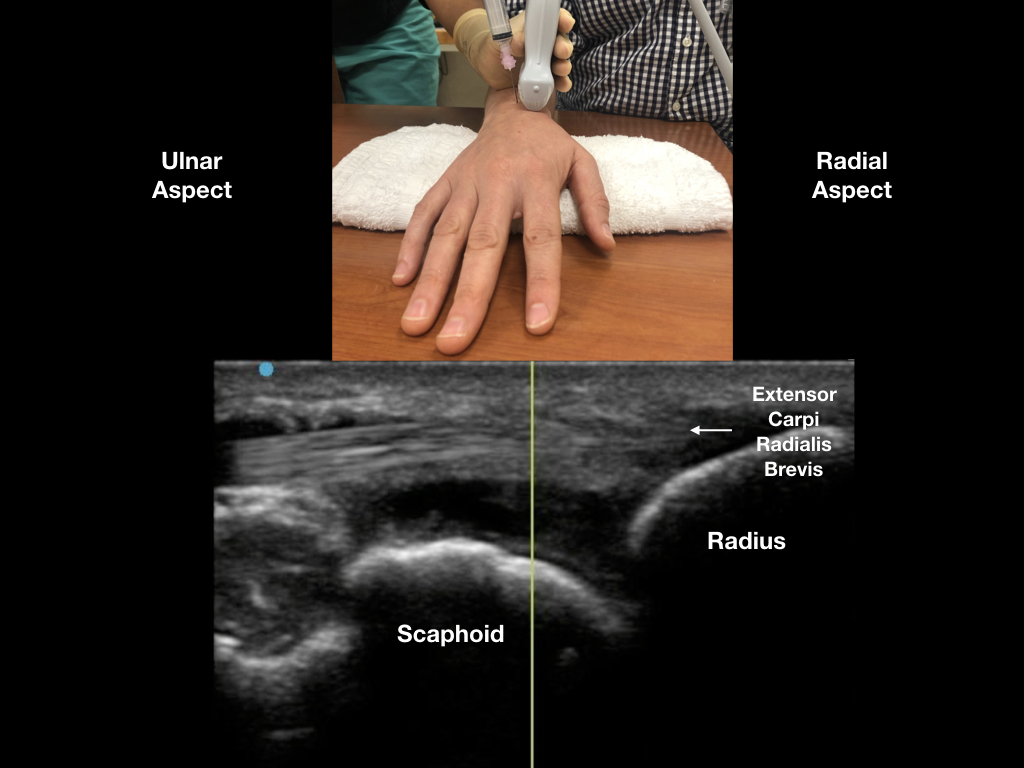

Figure 4: With the ultrasound probe covering the extensor carpi radials brevis, enter the swollen joint capsule with an out-of-plane technique. We recommend a steep needle angle of entry between Lister’s tubercle and the extensor carpi radials brevis. The procedure should be performed with sterile precautions (like any other joint aspiration).